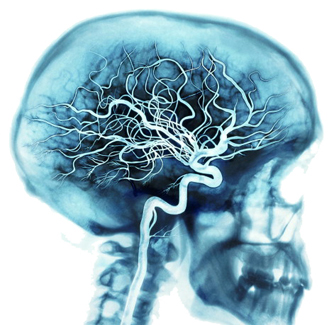

2. Supply lines

Your brain is nourished by one of your body's richest networks of blood vessels.

With each heartbeat, arteries carry about 20 to 25 percent of your blood to your brain, where billions of cells use about 20 percent of the oxygen and fuel your blood carries.

When you are thinking hard, your brain may use up to 50 percent of the fuel and oxygen.

The whole vessel network includes veins and capillaries in addition to arteries.